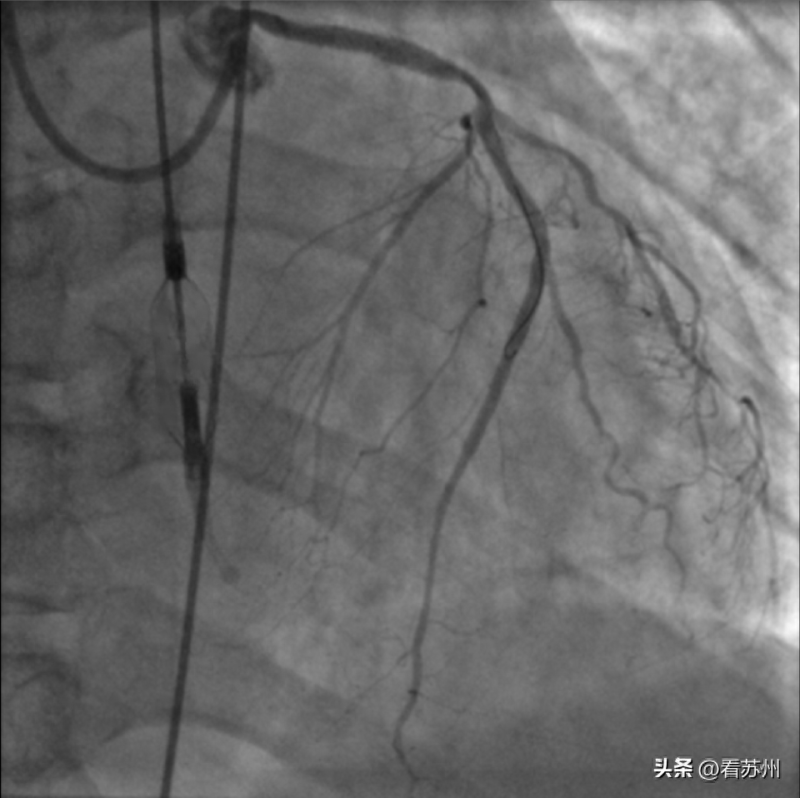

复旦大学附属中山医院葛均波院士团队成功在新一代介入泵(心擎医疗)支持下为一名男性患者完成高风险经皮冠脉手术(HRPCI)。

本次高危PCI手术的顺利开展,初步证实了心擎医疗的新一代介入泵在辅助高危PCI手术中的安全性和有效性,代表世界最小介入式人工心脏正式迈向临床,具有重要意义。

“我们的产品只有9Fr的介入尺寸,是目前世界上最小的介入尺寸。在介入的时候可以折叠,极大程度缩小了介入尺寸。这样的尺寸可以极大降低创伤性,减少各种血管并发症,包括复杂性病变硬化等问题。”心擎医疗市场与临床部马经理告诉记者,“折叠叶轮的优势之一,是可以提供均值3.5 L/min以上的流量。同时,我们还做了有限元的结构力学分析,可以对运行强度做优化。”

“术后介入泵顺利回撤至鞘内撤出,仅使用单把血管缝合器就完成了股动脉穿刺处止血,患者6小时后即下床活动,无血管并发症。”葛均波说,“手术是成功的。”

目前,患者的术后恢复情况良好,血常规、肝肾功能等指标均未见明显异常,术后动脉血压维持在130/80 mmHg,术后心超显示左室射血分数改善至36%,未见主动脉瓣及二尖瓣损伤,已经顺利出院。